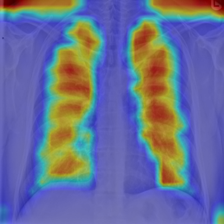

4.7.2 Activation Response Maps

As shown in Fig. 9, given the text lungs, we can find that the activation maps can accurately highlight the target regions. Therefore, we can achieve a higher performance on the downstream tasks. However, the activation maps are imperfect, as the background regions are also highlighted.